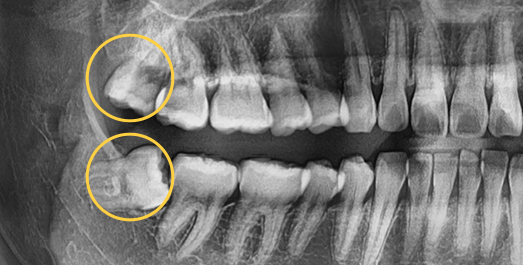

• 각도를 가지고

숨어있는 사랑니

• BEFORE

• AFTER

치료기간 : 2023.12.22